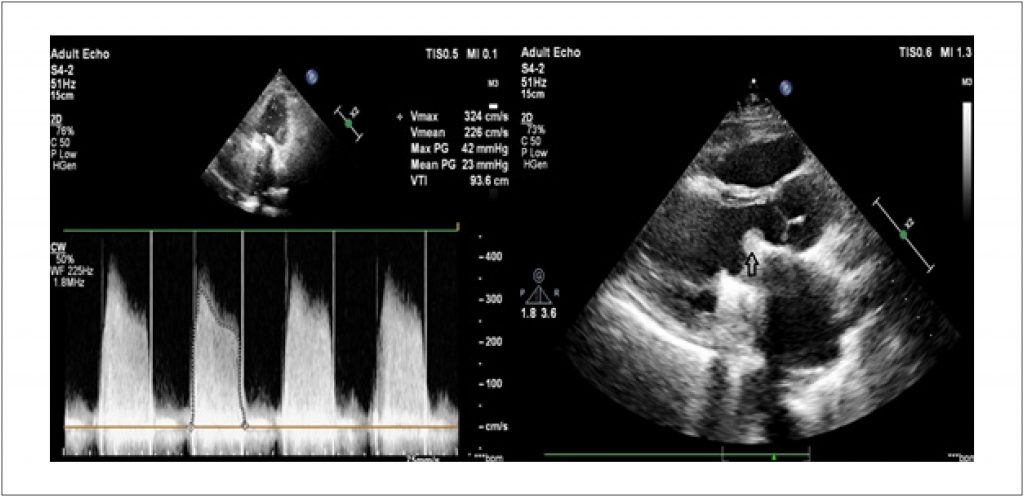

Mechanical Mitral Valve Thrombosis in a Patient with COVID-19 Infection

We present a case of a COVID-19 infected patient with thrombosis of the mechanical mitral valve.